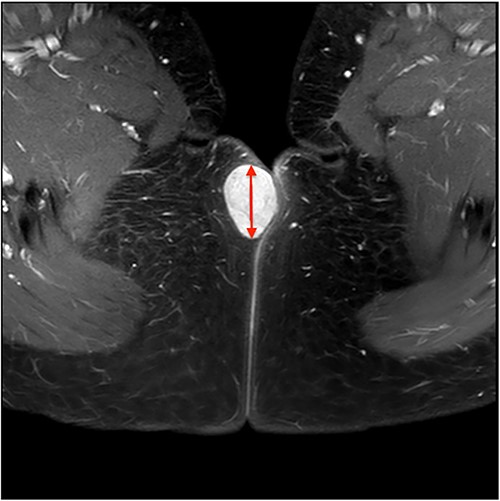

On ultrasound, the lesion was described as a heterogeneous mass with complex internal vascularity, highly suggestive of malignancy. Further workup with magnetic resonance imaging (MRI) demonstrated a 36 × 28 × 23 mm mass at the posterior aspect of the right vulva visible on the coronal (Fig. 1) and axial view (Fig. 2). The lesion was abutting the skin surface but separate from the anus, vagina and urethra, and suspicious for soft-tissue sarcoma.

Pre-operative diagnosis is particularly challenging because of the wide variety of tissues in the pelvic and perineal areas. A recent publication suggests a low-grade sarcoma should be a differential diagnosis for any perineal mass [10]. This author also reported the benefit of MRI with intravenous contrast as an imaging modality for the characterization and diagnosis of perineal soft-tissue lesions and assessing the position, depth and anatomical relationships of the lesion. On MRI, fibroadenomas typically appear as smooth masses with high signal intensity on T2-weighted images. However, fibroadenomas may have a contrast-enhancement pattern suggestive of malignancy in up to one-third of cases [11]. Definitive diagnosis often requires excisional biopsy or image-guided biopsy. On histopathology, fibroadenomas are comprised of glandular epithelium and specialized interlobular stroma of the terminal ductal lobular unit.